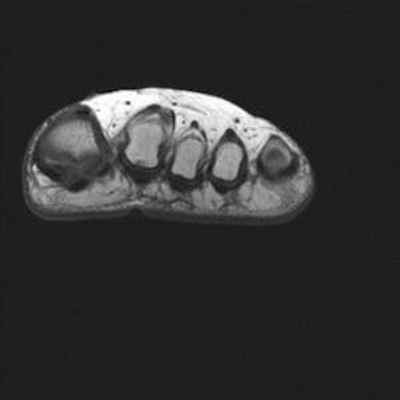

Боль в переднем отделе стопы правой ноги у пациентки 19 лет, в области головки 2-ой плюсневой кости.

Головка 2-ой плюсневой кости выглядит сплюснутой и расширенной с правой стороны в связи с болезнью Фрейберга.

Отсутствие внутрикостной отёчной инфильтрации по краям суставной щели плюснефалангового сустава. Напротив, следует отметить наличие внутрисуставного выпота.

Отсутствие бурсита между головками плюсневых костей или под ними.

Не обнаружено невромы Мортона или тендовагинита.